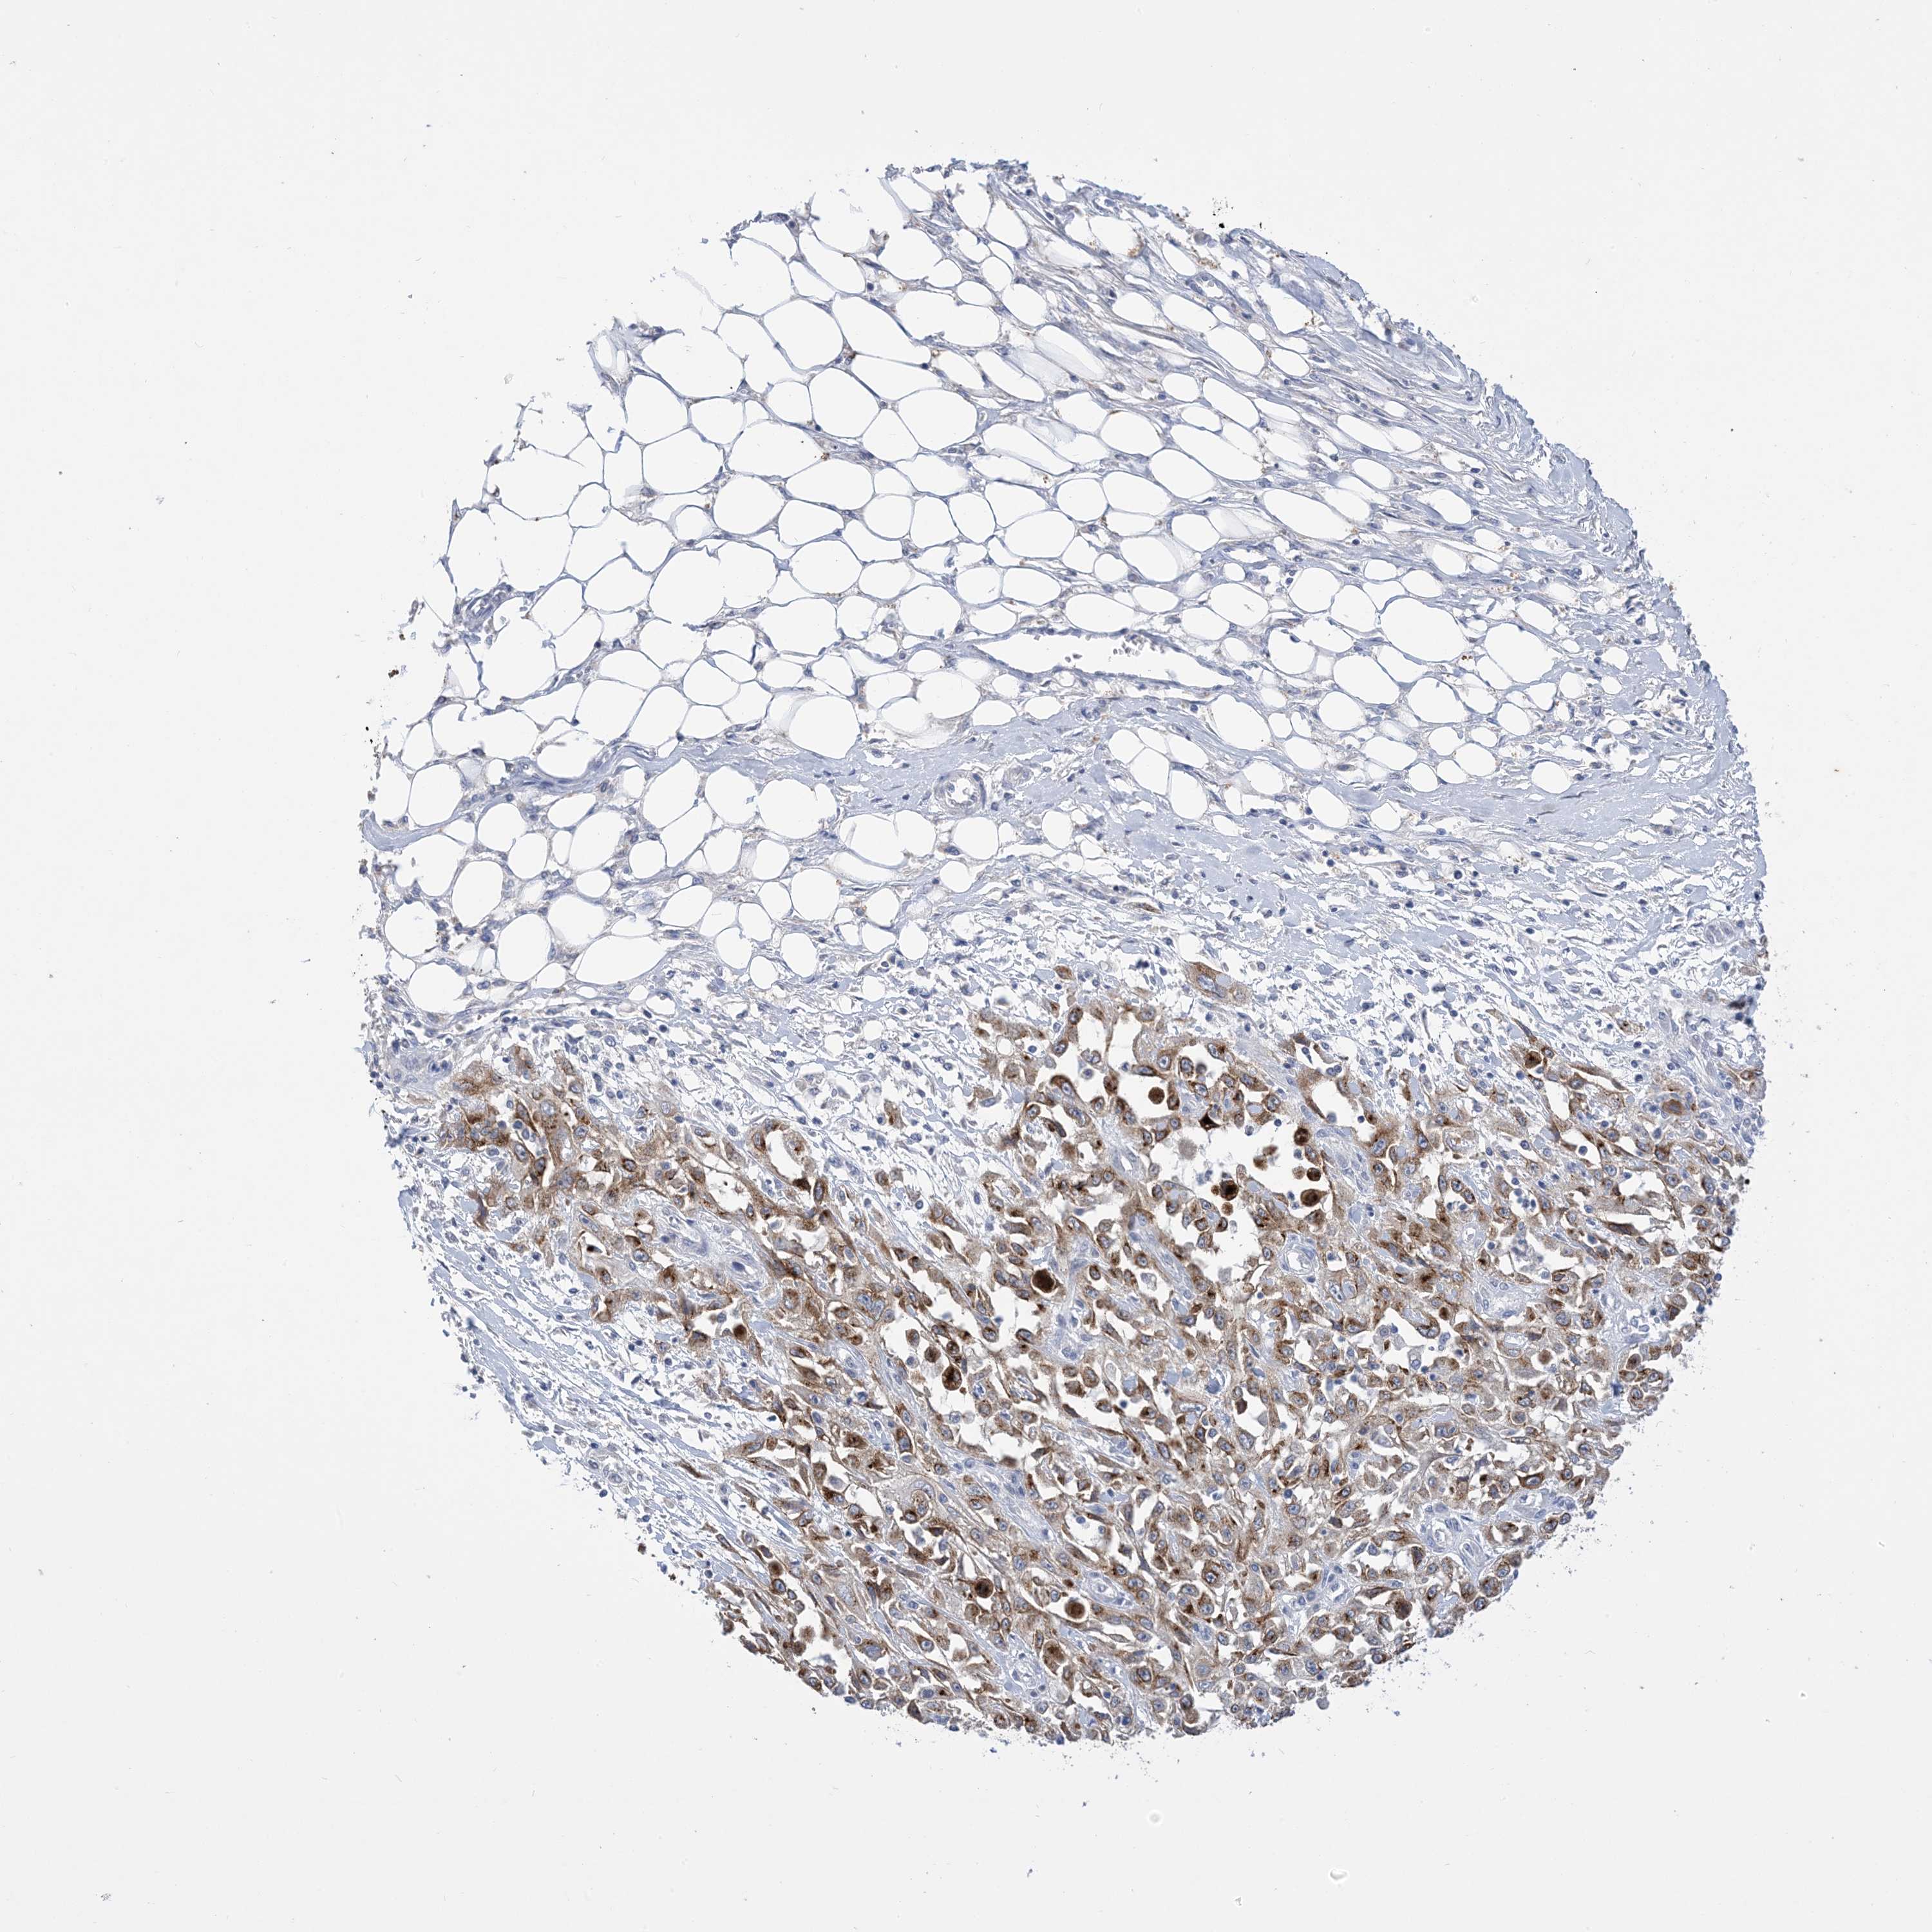

Basal cell and squamous cell cancer

SKIN CANCER - Protein expressioni

A mouse-over function shows sample information and annotation data. Click on an image to view it in a full screen mode. Samples can be filtered based on level of antibody staining by selecting one or several of the following categories: high, medium, low and not detected. The assay and annotation is described here.

Each image is clickable and will lead to virtual microscopy that enables deeper exploration of all samples and also displays staining intensity scores, fraction scores and subcellular localization as well as patient and tissue information for each sample.

Antibody CAB037328

Squamous cell carcinoma, metastatic, NOS